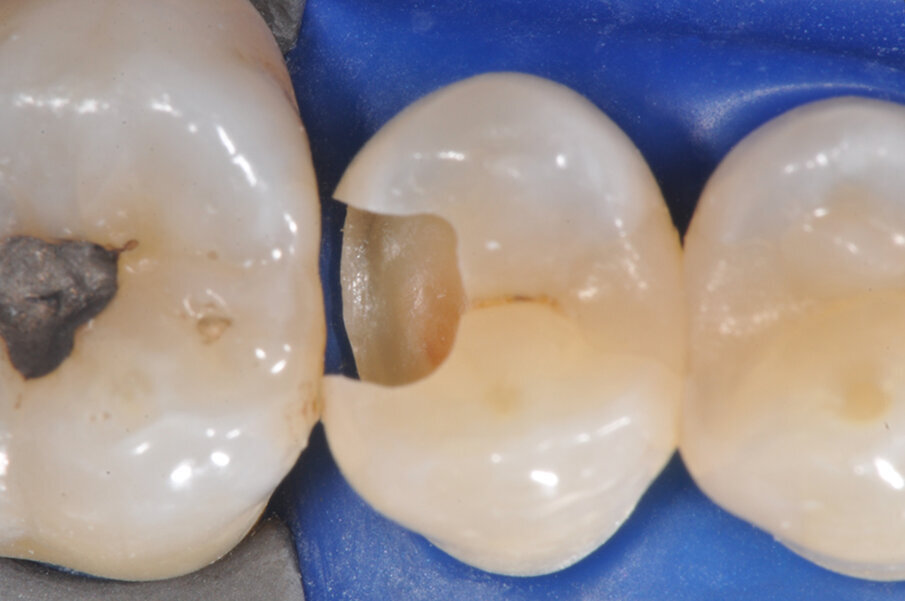

Viene posizionato un cuneo con matrice allo scopo di proteggere il dente aprossimale (Fig. 2). La cavità è stata preparata, la carie asportata, i margini cavitari devono essere rifiniti (Fig. 3). Vengono rimossi il cuneo e la matrice per meglio rifinire il gradino cervicale e per valutare che tipo di cuneo utilizzare (Fig. 4). Ai fini di migliorare l’adattamento della matrice viene utilizzata una striscia abrasiva in plastica di grana media (Fig. 5).

Viene posizionata una matrice Fusion FX175 e inserito un cuneo Fusion FXOR da vestibolare, per favorire la chiusura della matrice nell’angolo tra gradino cervicale e parete assio-pulpare vestibolare, resa difficile dalla rotazione dell’elemento 1.5 (Fig. 6). Si posiziona l’anello separatore FX400 - si noti il perfetto adattamento della matrice alle pareti assiali e al gradino cervicale. Quest’ultimo grazie soprattutto all’azione delle alette in silicone del cuneo (Fig. 7). Un’altra inquadratura evidenzia la profondità della cavità pulita (Fig. 8).